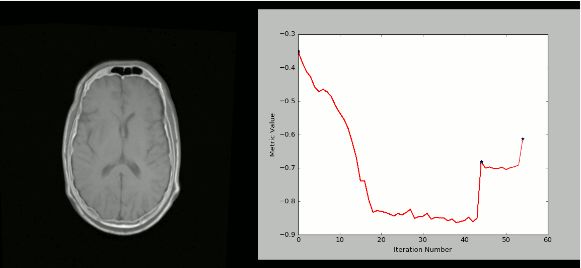

8. SimpleITK

ITK(Insight Segmentation and Registration Toolkit)是一个“开源,跨平台系统,为开发人员提供了一套用于图像分析的广泛软件工具。SimpleITK是一个基于ITK构建的简化层,旨在促进其在快速原型设计,交易以及解释语言方面的应用。”它也是一个图像分析工具包,具有大量组件,支持一般过滤操作,图像分割和配准。SimpleITK是用C ++编写的,但它可用包括Python在内的大量编程语言进行操作。

有大量的Jupyter Notebook说明了SimpleITK在教育和研究活动中的应用。Notebooks使用Python和R编程语言演示如何使用SimpleITK进行交互式图像分析。

使用SimpleITK和Python创建可视化的严格CT / MR配准过程: